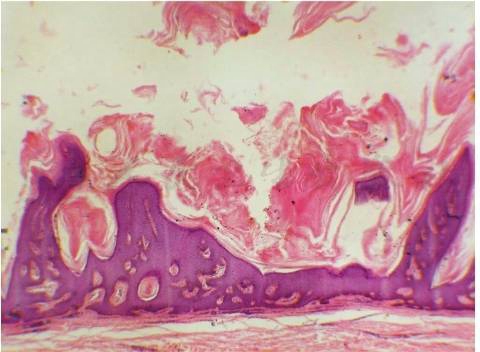

角化型:有明显的角化过度及乳头瘤样增生。增多的角质填塞在表皮扭曲的凹陷部分,有时在切片中呈角质囊肿状,被称为假角质囊肿。大部分表皮细胞是外观正常的棘细胞(鳞状细胞),少数是散在的小群基底样细胞(图1)。

图1脂溢性角化病病理(一)